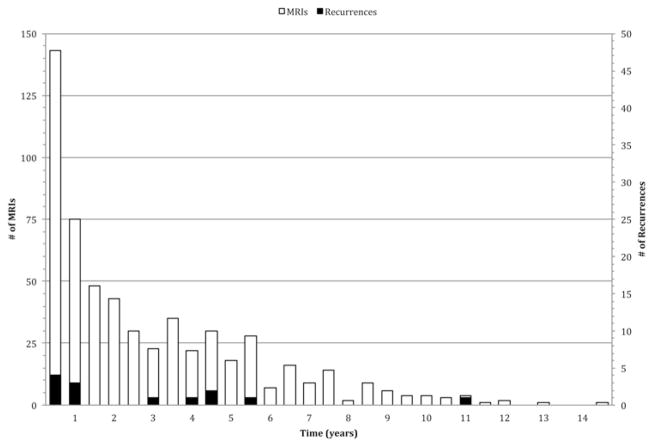

Given the lack of any clinical symptoms associated with recurrence after GTR in our patient population and the generally indolent growth characteristics of WHO Grade I glial and glioneuronal lesions, we propose a post-operative MRI surveillance schedule that is substantially less intensive than our current protocol. Although the absolute number of recurrences in our population was small, plotting the timing of recurrences provided a sense of when recurrences generally occur (Fig. 3). Recurrences appeared to cluster within year 1 (n = 7), between years 3 and 5 (n = 5), and at approximately 10 years (n = 1). Four of the recurrences occurred in the first 6 months at 2.9, 3.4, 3.5, and 4.8 months. We do not believe these early recurrences represented residual tumors, as the same criteria to define GTR were used to analyze postoperative imaging. In addition, a median time to recurrence of 6.4 months was previously reported following GTR for pilocytic astrocytomas.4 Therefore, we would recommend the following postoperative MRI schedule: (postoperative time = time 0) 1–3 days; and 3 months; and 1, 2, 5, and 10 years.

Fig. 3.

Time point of recurrence for 13 children after GTR of low-grade glial tumors.

If this schedule were applied to our data set, assuming the actual time the recurrence was detected was the earliest radiographic sign of recurrence (± 1 month), 6 of the recurrences would have been detected with no delay, and the remaining 7 recurrences would have been detected with delays ranging from 1.1 to 51.5 months, with an average delay of 9 months. However, it is highly likely that both the largest individual delays and the estimated average delay in detection are gross overestimates. The patient with the greatest hypothetical delay to detection using our proposed protocol showed the first radiological sign of recurrence at 128.5 months. However, no MR scan was obtained at 120 months, which may have reduced the detection delay. The next greatest hypothetical delay to detection of 25 months occurred for a patient who did not undergo the first follow-up surveillance MRI until postoperative Month 35. Similarly, a patient with a hypothetical 15.5-month delay to recurrence detection had surveillance MRI performed 2 weeks and 4 years postoperatively, with no intervening scans. Surveillance MRI at Month 24 in our proposed schedule may have identified both of these recurrences.

Figure 4 plots the numbers of MR scans and recurrences over time. By Year 5, a total of 467 MR scans were acquired, and 11 recurrences were detected. Based on the average cost of an MR scan with contrast, we were able to calculate a cost of $72,555 per recurrence at 5 years. Under the current institutional schedule, at 5 years, 10 scans per patient would have been obtained for a total of 670 MR scans, which corresponds to a cost per recurrence of $104,094. Under the proposed plan, only 5 scans per patient would have been acquired over the 5-year postoperative period, for a total of 335 MR scans at an estimated cost per recurrence of $52,047. The costs per recurrence under our proposed schedule represent reductions of $20,508 and $52,047, respectively, compared with the estimated cost per recurrence based on the actual and theoretical numbers of scans that would have been performed under the current institutional protocol.

Fig. 4.

Bar graph plotting the number of MR scans (unshaded) and recurrences (shaded) in 6-month periods. A cost per recurrence value can be estimated by comparing the number of MR scans and associated cost to the number of recurrences detected over time.